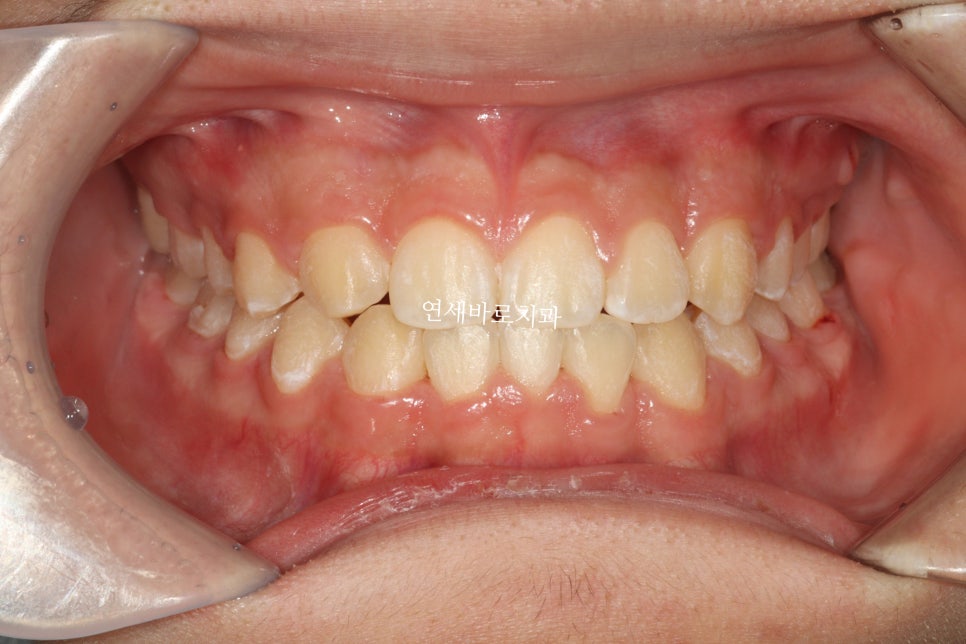

교정이 마무리된 지난주 모습입니다.

치아가 하나는 선천적으로 없었고, 아래 앞니 하나는 일부러 발치를 했습니다

이런식으로 눈속임 교정치료를 통해 치아를 배열했습니다

아마 일반인 분들은 일상생활속에서는 이상함을 느끼지 못할 정도라 생각합니다.